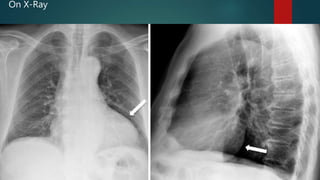

On X-Ray

• 36.

• 37.